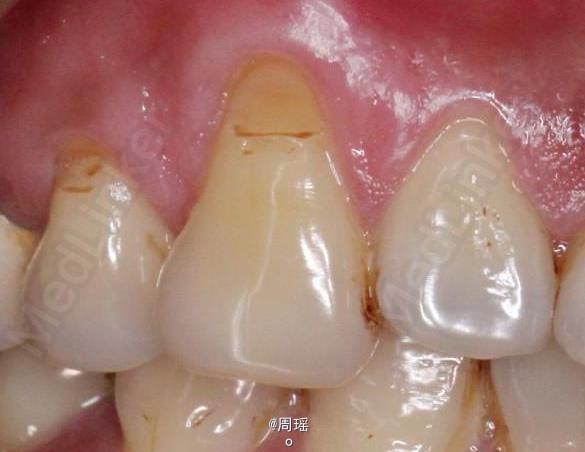

树脂修补

随访 讨论

效果很好,患者满意。